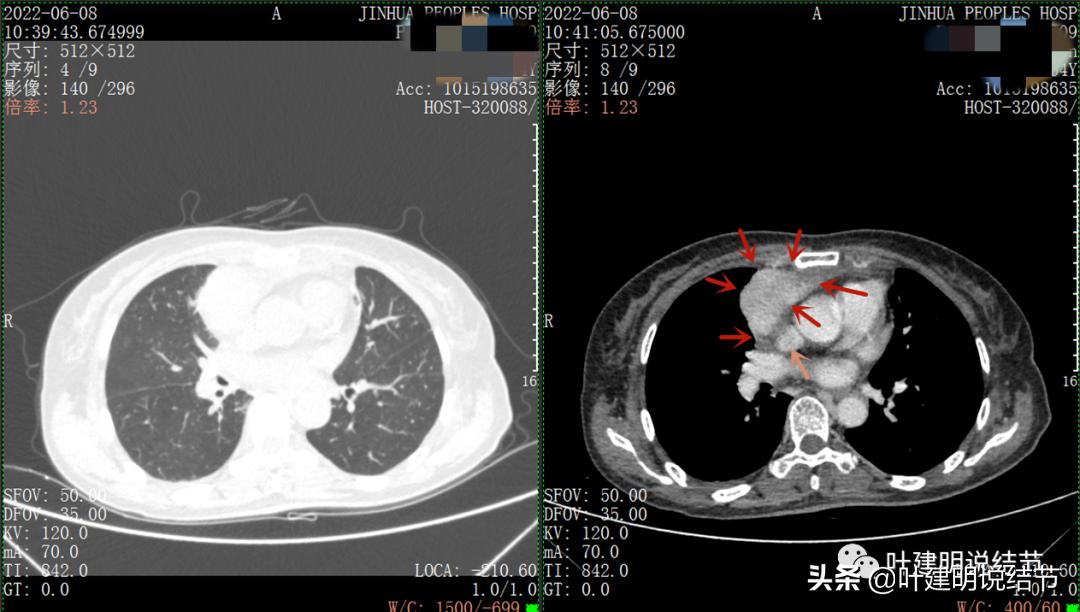

以下图片左侧是肺窗,右侧是纵隔窗。红色箭头示病灶,桔色箭头示无名静脉,黄色箭头示支气管,砖色箭头示上腔静脉,蓝色箭头示主动脉,紫色箭头示肺动脉。

病灶纵隔胸膜侧非常光滑,说明来源于纵隔

粉色箭头示淋巴结可能